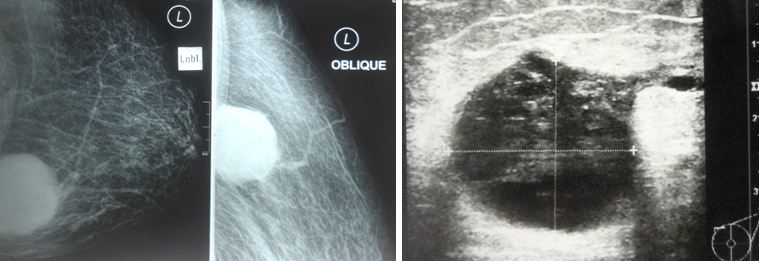

Ros is 55-year-old Indonesian lady. In early January 2016, she found a lump in her left chest just above her breast. A doctor in her hometown requested her to do a biopsy. She refused. She did nothing after that.

Some eight months later, Ros had no choice but had to consult the doctor again since the lump had grown bigger.

A biopsy was done, followed by a total left mastectomy.

Histopathology confirmed a malignant tumour — ER negative, PR negative and HER-2 positive.